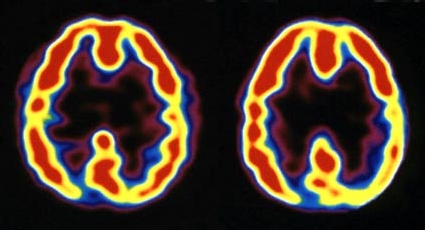

¿Pero qué sucede en el cerebro cuando éste se ve sometido a tales estímulos? Tal y como comenta el segundo artículo de Slate, el científico Andrew Newberg de la Universidad de Pennsylvania estudió los cerebros de monjes franciscanos y budistas dedicados a la meditación descubriendo que en ellos había una mayor actividad en el lóbulo frontal (asociado con la concentración y la atención), mientras que el lóbulo parietal, vinculado con la información sensorial, tenía escasa actividad en estas personas.

En Tendencias21 ya explicamos a este respecto que esta investigación reveló asimismo que la actividad del encéfalo se modifica con las actividades espirituales. La actividad se intensifica en la parte frontal del cerebro cuando se desarrolla la concentración propia de la meditación o de la oración. Al mismo tiempo, se reveló un descenso de la actividad en la región de los lóbulos parietales, que es la que desempeña la función fundamental para ubicarnos en el espacio y la que permite al yo distinguirse de los demás.

Este descenso de la actividad en los lóbulos parietales origina percepciones espaciales anormales y la pérdida del sentido habitual de uno mismo que se tiene en estado de vigilia. Es en ese momento cuando se posibilita la así llamada experiencia mística, que es la que permite a un sujeto trascender su identidad individual e identificarse con la totalidad que se supone sustenta al universo físico conocido.

Por otro lado, investigaciones realizadas por Richard Davidson, de la Universidad de Wisconsin, con monjes tibetanos demostraron también que los patrones de electroencefalogramas de estas personas presentaban mayores niveles de ondas gamma durante periodos de meditación, e incluso después de éstos.